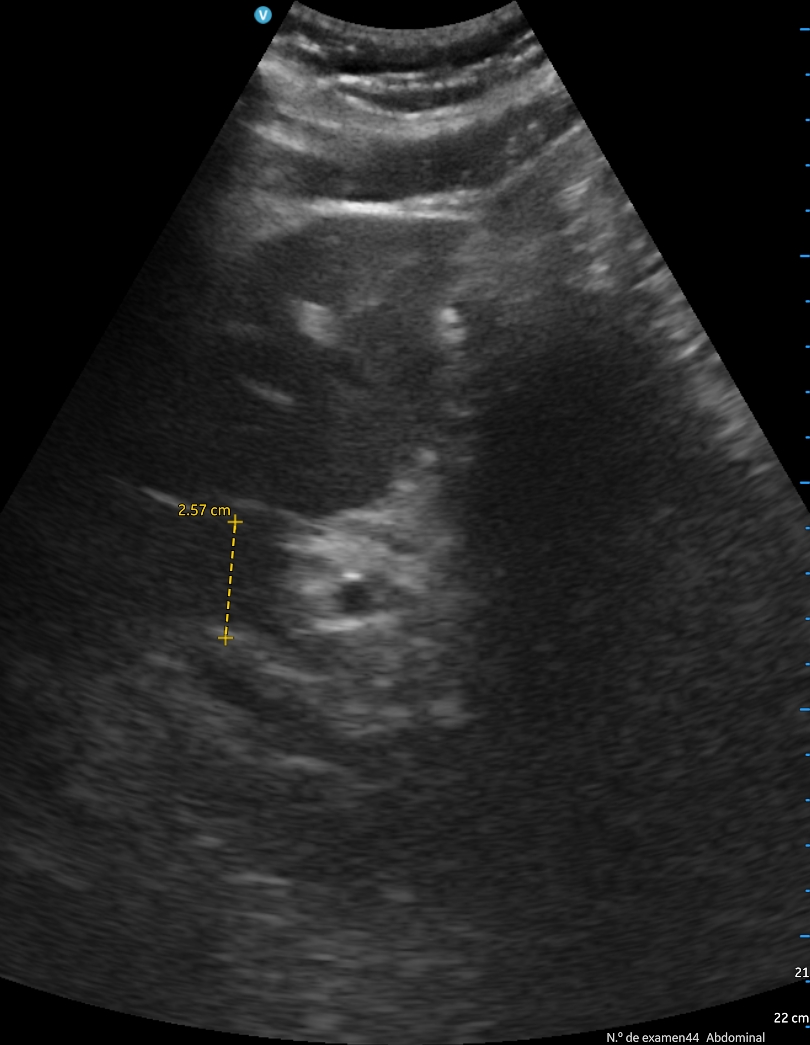

Se aprecia atelectasia lobar media con derrame pleural derecho de unos 150 cc, signo de la medusa. Líneas B en patrón B3 en ambas bases. Cavidades cardiacas normales con correcto funcionamiento valvular, adecuada contractilidad sin indicios de derrame pericárdico. Aumento de vena cava de 2,57 cm no colapsable.

A los 2 días, el paciente presenta empeoramiento de clínica, con disminución SpO2 a 90%, persistencia de fóvea intensa y disnea de reposo. Se revalora ecográficamente encontrando aumento de derrame pleural, ahora 500 cc, una vena cava de 3,27 cm no colapsable y derrame pericárdico. Finalmente se decide derivación hospitalaria.